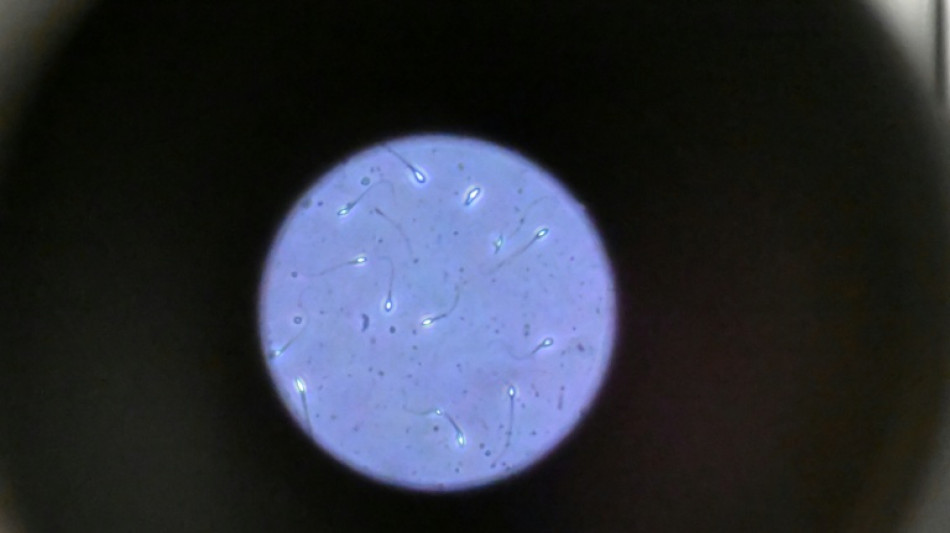

Dans l'espace, les spermatozoïdes ont du mal à trouver leur chemin vers l'ovule en raison de la microgravité, qui perturbe aussi le développement des embryons, selon une étude publiée jeudi dans Communications Biology.

"Les spermatozoïdes doivent activement trouver leur chemin vers l'ovule et cette étude est la première à tester leur capacité à le faire dans des conditions semblables à ce qui se passe dans l'espace", explique à l'AFP Nicole McPherson, autrice principale de l'étude et chercheuse à l'Université d'Adelaïde (Australie).

Les chercheurs ont testé successivement du sperme de souris et humain dans ce dispositif placé dans un appareil en constante rotation pour simuler la microgravité.

Les gamètes ont été environ 50 % moins performants pour naviguer à travers ce parcours que sous la gravité terrestre. Cela équivaut à une baisse de 30% du taux de fécondation réussie, selon les résultats de l'étude.